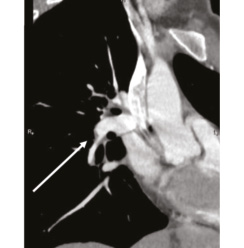

В 1993 г. на основании характерных признаков электрокардиограммы (ЭКГ) при профилактическом обследовании диагностирован феномен Вольфа–Паркинсона–Уайта. Клинических проявлений, снижающих качество жизни, пациентка не отмечала. К врачам далее не обращалась. В связи с появлением в 2015 г. одышки, перебоев в работе сердца, сердцебиения наблюдалась у участкового терапевта с диагнозом: ишемическая болезнь сердца, гипертоническая болезнь. Эхокардиография (ЭхоКГ), нагрузочные тесты не проводились. На фоне приема лозартана 25 мг/сут достигнуты целевые значения АД. В январе 2017 г. в связи с зарегистрированным на ЭКГ пароксизмом тахикардии с узкими комплексами QRS пациентка в порядке скорой помощи поступила с диагнозом «пароксизмальная суправентрикулярная тахикардия» в ЦРБ, где ритм был медикаментозно восстановлен. Далее в краевой больнице проведено внутрисердечное электрофизиологическое исследование и по его результатам – радиочастотная аблация дополнительных проводящих путей. Послеоперационный период протекал без осложнений. Однако в июне 2017 г. вновь появилась одышка при выполнении привычного объема физической нагрузки. По данным ЭКГ и рентгенограммы органов грудной клетки патологии не выявлено. Вскоре появилось кровохарканье (в течение 3 дней), и пациентка была направлена к фтизиатру, которым исключен туберкулез легких. 27.07.2017 на фоне значительного усиления одышки, выраженной тахикардии она потеряла сознание и в порядке скорой помощи доставлена в дежурный стационар, где травматологом и неврологом исключены сотрясение головного мозга и закрытая черепно-мозговая травма. Пациентка отпущена домой. В связи с сохраняющейся одышкой при подъеме на один лестничный пролет в августе 2017 г. по собственной инициативе она обратилась к кардиологу. При проведении ЭхоКГ выявлены увеличение правых камер сердца и признаки их объемной перегрузки. С предварительным диагнозом ТЭЛА пациентка направлена в дежурный стационар, где в экстренном порядке проведена спиральная компьютерная томография (СКТ) с контрастированием легочной артерии. Выявлены признаки легочной тромбоэмболии крупных и средних ветвей легочной артерии (ЛА) с обеих сторон (рис. 1–4). При целенаправленном сборе анамнеза выяснилось, что в течение 3 лет (с 2014 г.) пациентка принимает Линдинет 20 мг – монофазный пероральный контрацептив (этинилэстрадиол + гестоден), назначенный гинекологом с целью контрацепции. По данным ультразвукового исследования вен нижних конечностей выявлен тромбоз суральных вен справа. Линдинет отменен. На фоне лечения антикоагулянтами (гепарин, эноксапарин) состояние женщины несколько улучшилось. Она переведена на варфарин, который далее заменен на апиксабан в дозе 10 мг 2 раза в день.

Рис. 3: а – тромбы в нижнедолевой ветви левой ЛА и нижнедолевой ветви правой ЛА; б – сохраняется тромбоз нижнедолевой ветви правой ЛА. | |

Рис. 4: а – тромбы в левой ЛА и ее ветвях; б – тромбоза левой ЛА (нисходящей ветви) не выявлено, сохраняется тромбоз нижнедолевой ветви левой ЛА. | |

По данным чресприщеводной ЭхоКГ тромбоза камер сердца не обнаружено, однако уровень D-димера – более 250 мкг/л. Исследования в отношении патологии гемостаза выявили значительный дефицит протеинов С и S. Проведена замена апиксабана на ривароксабан 15 мг 2 раза в сутки с последующим переводом на прием ривароксабана 20 мг 1 раз в сутки в связи с большей биодоступностью последнего. Также с целью усиления антитромботического эффекта к терапии добавлен клопидогрел в дозе 75 мг в сутки. При проведении СКТ органов грудной клетки с контрастированием легочной артерии 26.09.2018 выявлена положительная динамика (см. рис. 1, б, рис. 4). Состояние стабилизировалось, рецидивы одышки прекратились. От имплантации кава-фильтра пациентка отказалась.